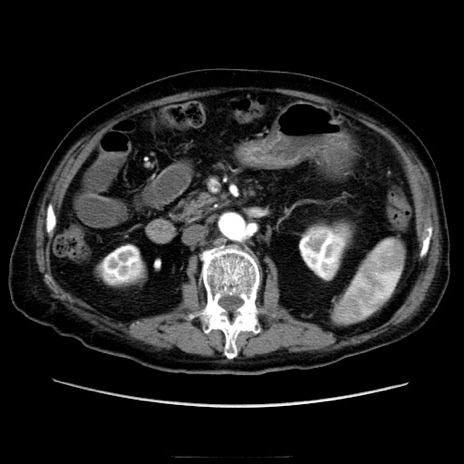

症例21(横断像)

【症例】70歳代男性

【主訴】腹痛

【現病歴】肝硬変・肝細胞癌にてかかりつけの方。約9時間前に食後より腹痛出現。症状が徐々に増悪し、嘔吐出現したため来院。

【既往歴】肝硬変、肝細胞癌(RFA、TACE後)

【身体所見】意識清明、表情苦悶様、BT 36℃、BP 129/78mmHg、P 88bpm、SpO2 97%(RA)、右上腹部から心窩部にかけて圧痛あり、反跳痛なし、筋性防御あり。

【データ】WBC 5800、CRP 0.16